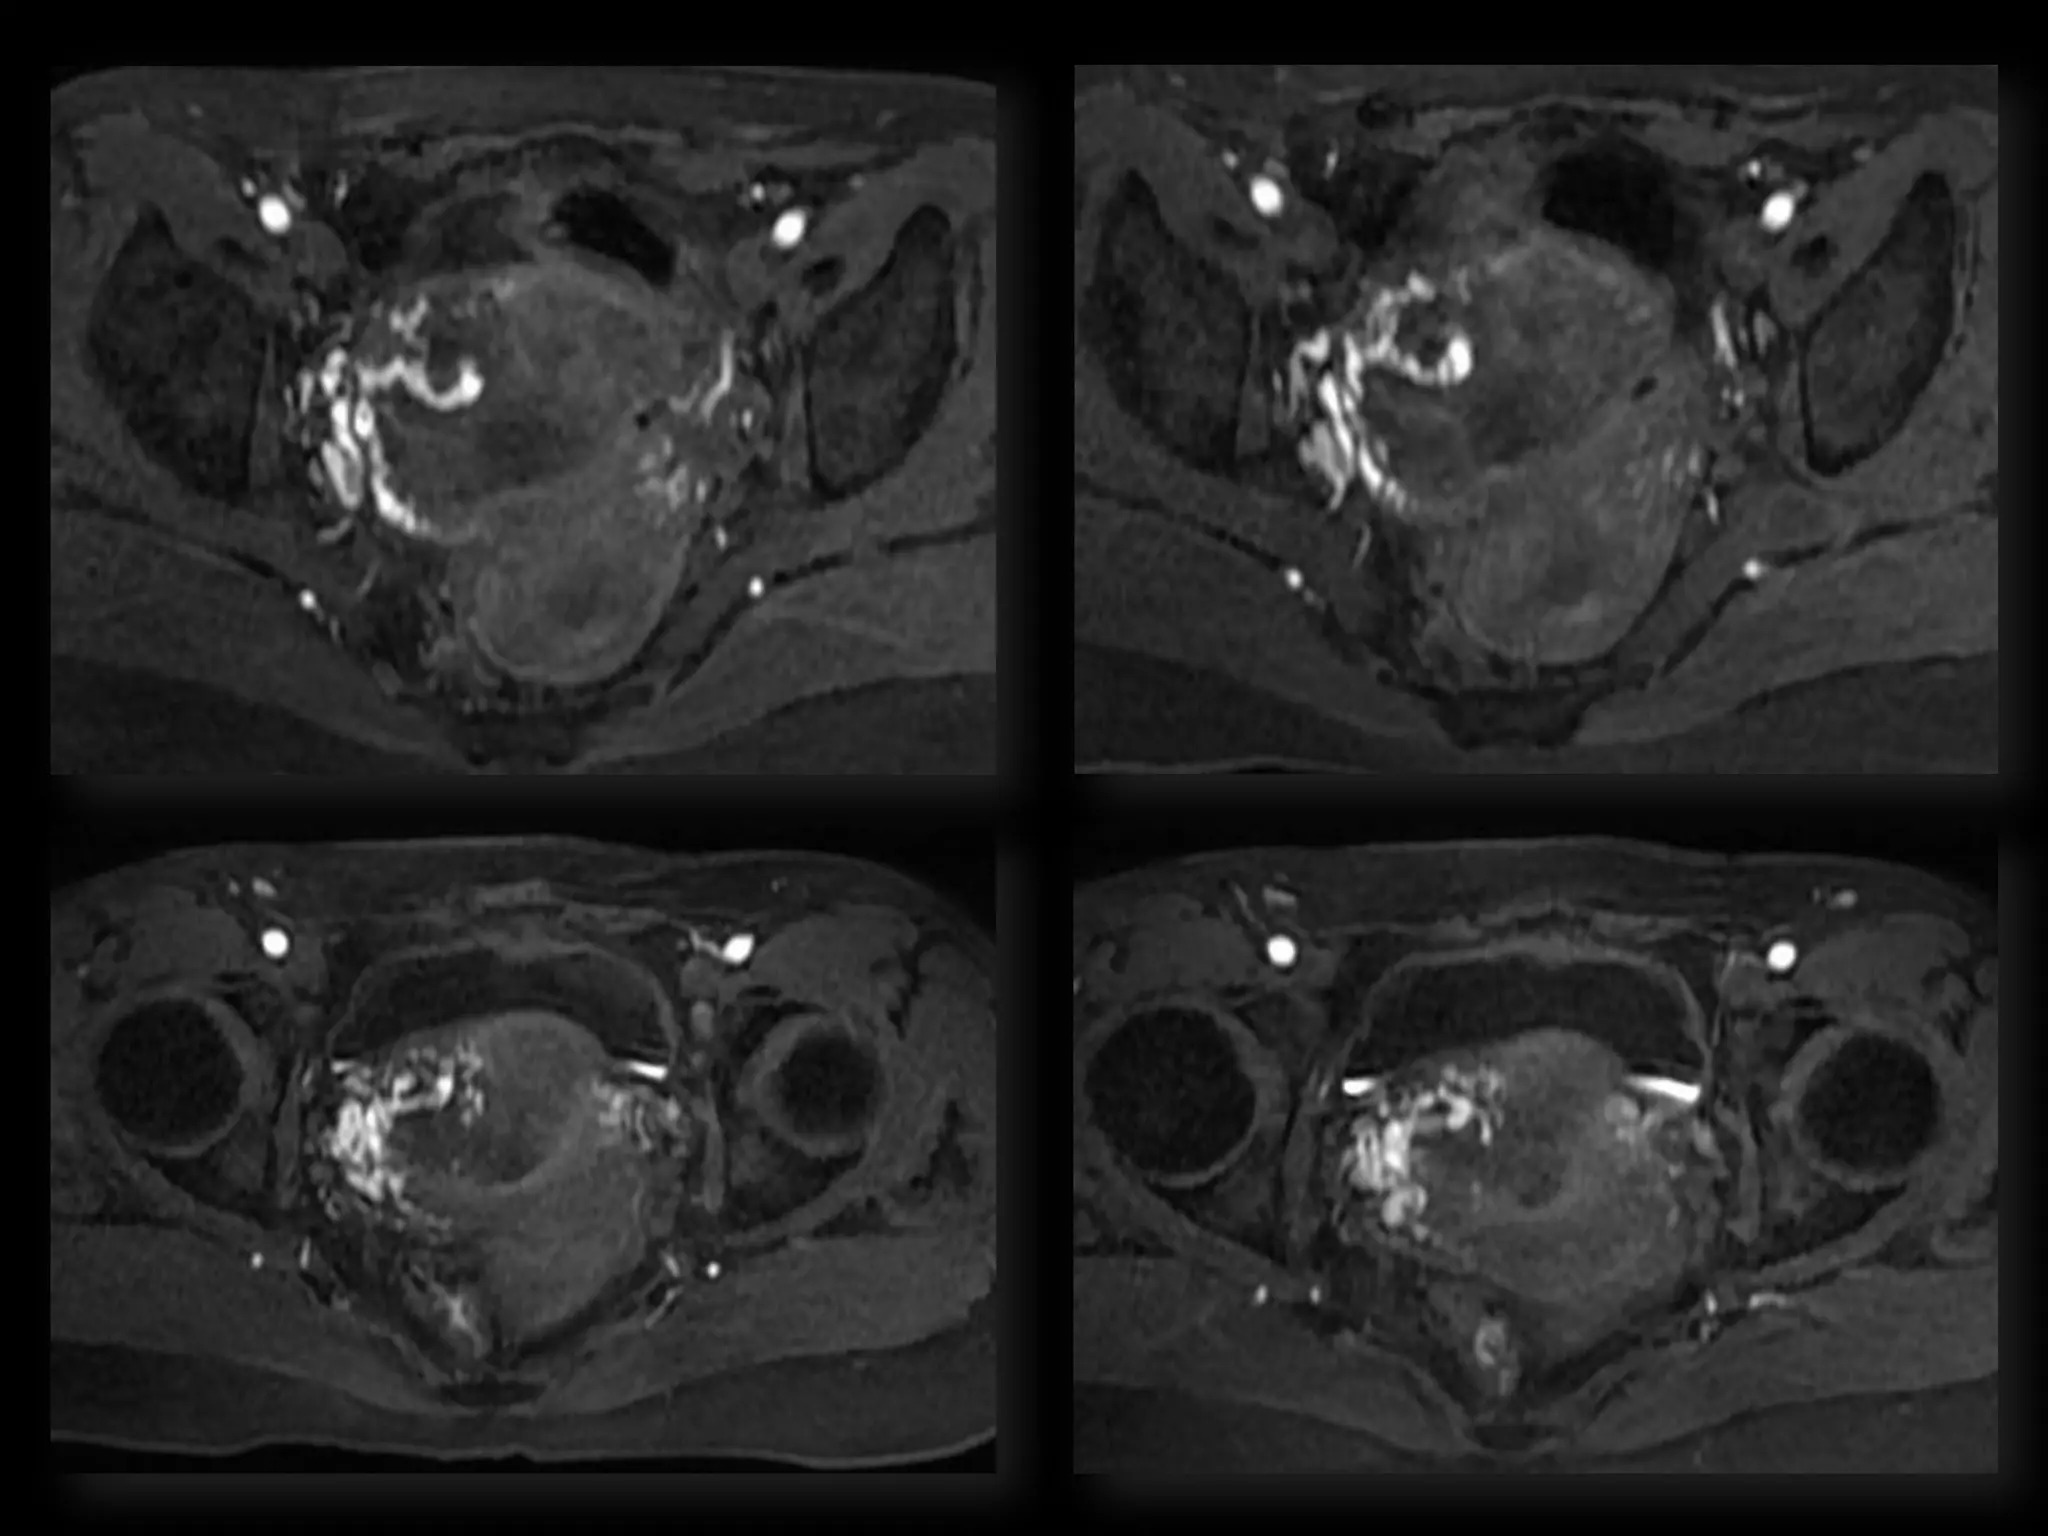

HISTORY โ€ข 42 yo female โ€ข Recent immigrant from China โ€ข C/O postcoital and intermenstrual bleeding โ€ข Abnormal GYN exam โ€ข Abnormal biopsy โ€ข Further imaging performed

MRI findings -Stage IIB with PET/CT - Stage IIIB Cervical Cancer

Role of MRImaging in Tx Stratification of GYN (Cervical) Cancer โ€ข Cervical Cancer โ€“ 2nd most common ca in women worldwide โ€“ Developing countries; pk 30-40 yrs โ€ข FIGO classification โ€“ revised in 2009 from just clinical to incorporate cross-sectional imaging (CT, MR) โ€ข Staging accuracy of MR 85-96% โ€“ Best test to assess tumor size and location; invasion into parametria, pelvic side wall, adjacent organs; local nodal enlgment โ€ข PET/CT helpful in staging advanced disease โ€“ Demonstrates unexpected sites beyond pelvis โ€ข Treatment options โ€“ Radical surgery - early stage (IA, IB1, IIA1) โ€“ Primary Chemo and Radiation โ€“ bulky IB2 or IIA2, or local advanced (IIB or greater) Sala et al. Radiology 2013; 266: 717.